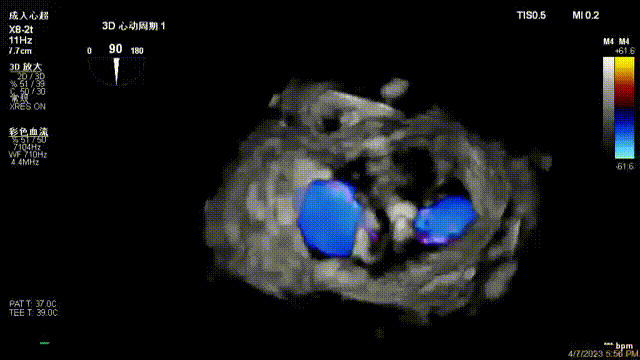

接受治療的是一例器質(zhì)性重度二尖瓣反流(DMR)患者,主訴“反復(fù)活動后胸悶,氣促3年余”。術(shù)前超聲顯示,雙房增大,二尖瓣脫垂伴重度反流,輕度三尖瓣反流,輕度肺高壓,升主動脈增寬。手術(shù)經(jīng)股靜脈-房間隔入路,采用全身麻醉插管,在TEE和DSA引導(dǎo)下完成房間隔穿刺。置入JensClip瓣膜夾系統(tǒng)后,在左房調(diào)整瓣膜夾的位置和軸向,后進入左室,在TEE引導(dǎo)下捕捉二尖瓣前后瓣葉,并關(guān)閉瓣膜夾。經(jīng)TEE反復(fù)確認手術(shù)效果后最終鎖定并釋放瓣膜夾。術(shù)后即刻超聲顯示瓣膜夾位置穩(wěn)定,功能良好,術(shù)前二尖瓣反流4+,術(shù)后0反流,肺靜脈逆流和左房壓都顯著好轉(zhuǎn),手術(shù)圓滿成功(以上數(shù)據(jù)都來源于醫(yī)院的臨床記錄)。術(shù)后患者狀態(tài)良好,目前已安排出院。

術(shù)后超聲顯示二尖瓣反流消失,瓣膜夾穩(wěn)定

出院前隨訪超聲